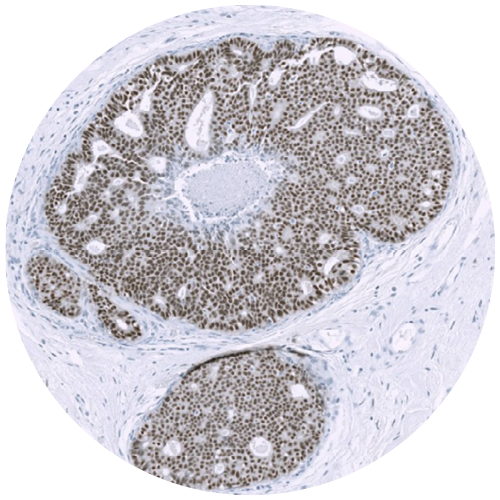

Physical IHC

ViewsML uses deep learning to eliminate physical staining, delivering virtual results in seconds at a fraction of the cost, all the while fitting into existing workflows.

Virtual IHC